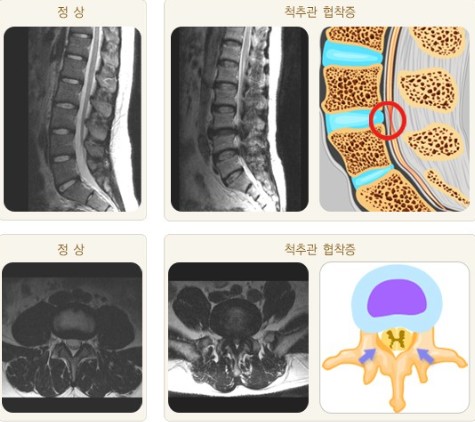

단순 방사선 검사 및 척추 자기공명영상을 촬영하여

추간판(디스크)의 변성과 척추 압박이 어느 정도인지를 알아보게 되는데,

특히 CT를 통해 척추관 옆에 위치하는 외측 함요의 협착 여부를 확인해야 합니다.

척수 조영술 상에는 척수 경막강이 전체적 혹은 부분적으로 좁아지거나

양측성으로 좁아져 모래시계 형태를 보이거나 조영제가 완전히 막힌 소견을 볼 수 있으며,

자기공명영상(MRI)에서는 압박된 부분이 더욱 잘 나타나게 됩니다.